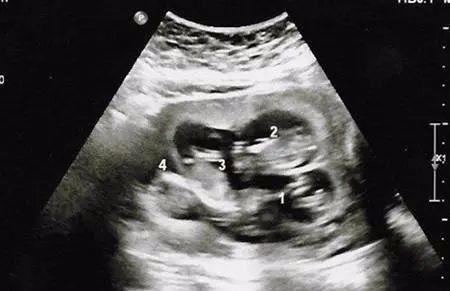

孕12周以后大如“临盆”,邻居亲朋都说不会是怀上双胞胎了吧,小蓉也只是笑笑,心想要是有就好了,当第一次产检时,医生却笑着恭喜说:“你是怀上了四胞胎了,我建议你最好减胎。”,全家人听完顿时愣住了。

小蓉的丈夫却愁坏了,要是生了四个儿子可怎么办,怕是70岁以前都不能有好日子过了。可是小蓉却执意要留下孩子,不愿意减胎。